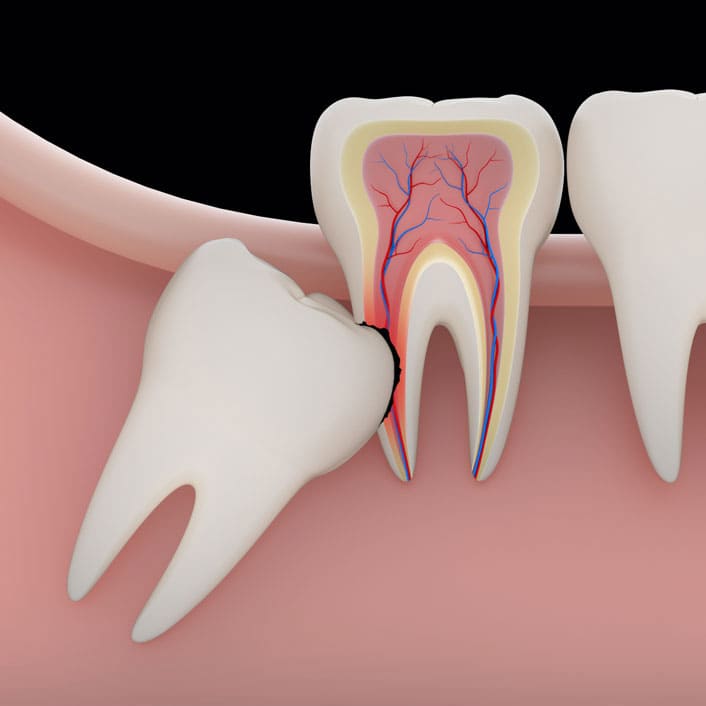

Wisdom teeth are a valuable asset to the mouth when they are healthy and properly positioned. Often, however, they cause problems that require their removal. When the jaw isn't large enough to accommodate wisdom teeth, they can become impacted. Impacted wisdom teeth may grow sideways, emerge only part way through the gum or remain trapped beneath the gum and bone.